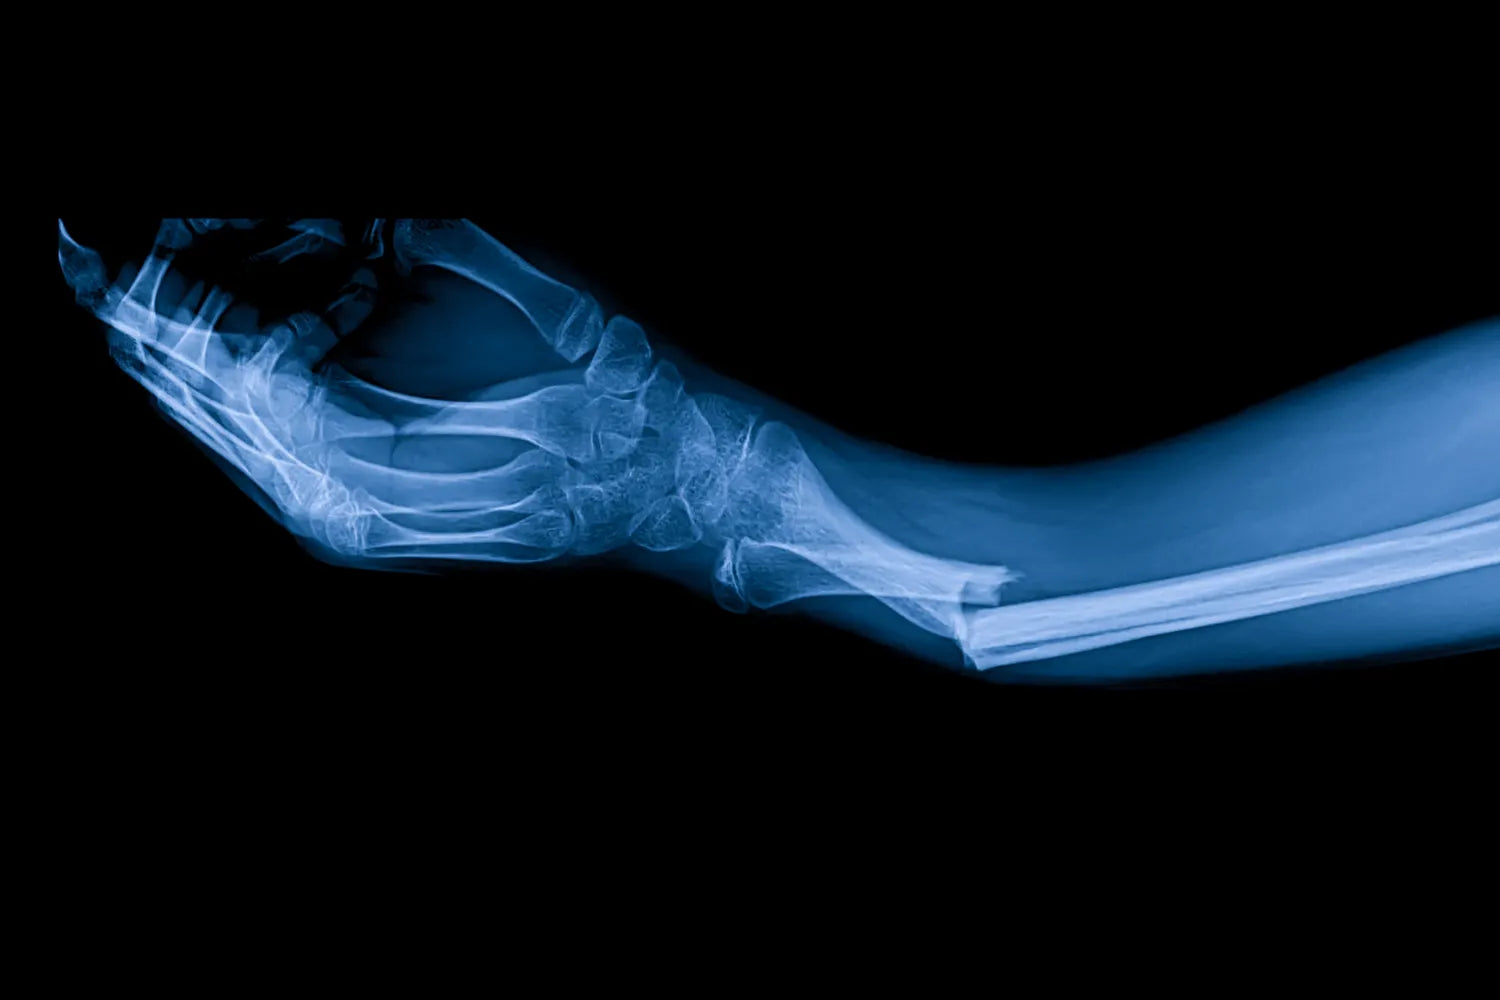

Does Collagen Help Heal Broken Bones?

If you’ve broken a bone, you already know that recovery can take six to eight weeks on average — sometimes even longer if you’ve broken something like your pelvis or tibia. Depending on which bone you’ve broken, that’s a lot of downtime, and you may be itching to get back to life as usual.

In the course of your internet research, you might have read something about collagen helping heal broken bones. Well, we’re here to deliver the facts. Read on to learn more about collagen, its role in bone repair, and whether taking collagen can actually speed up your recovery process.